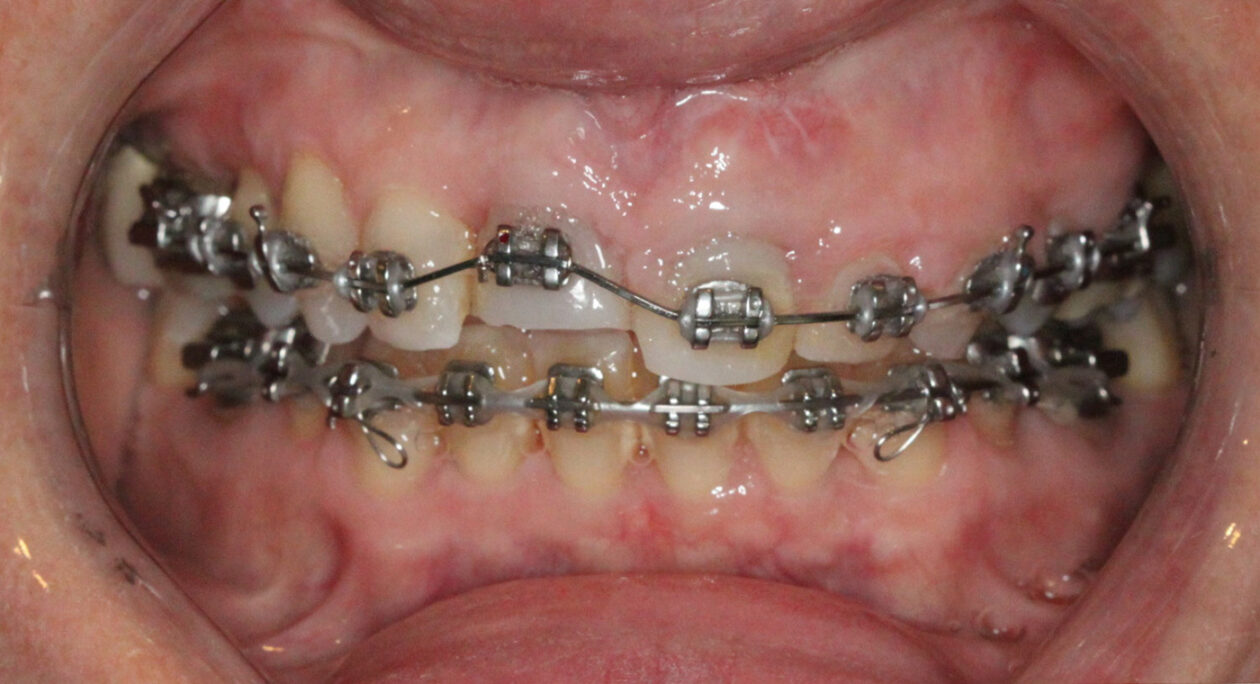

The special report presented below illustrates how orthodontic extrusion was successfully used to improve the periodontal architecture prior to the placement of two adjacent implants in the esthetic zone and thus allowed for a more ideal restorative result.